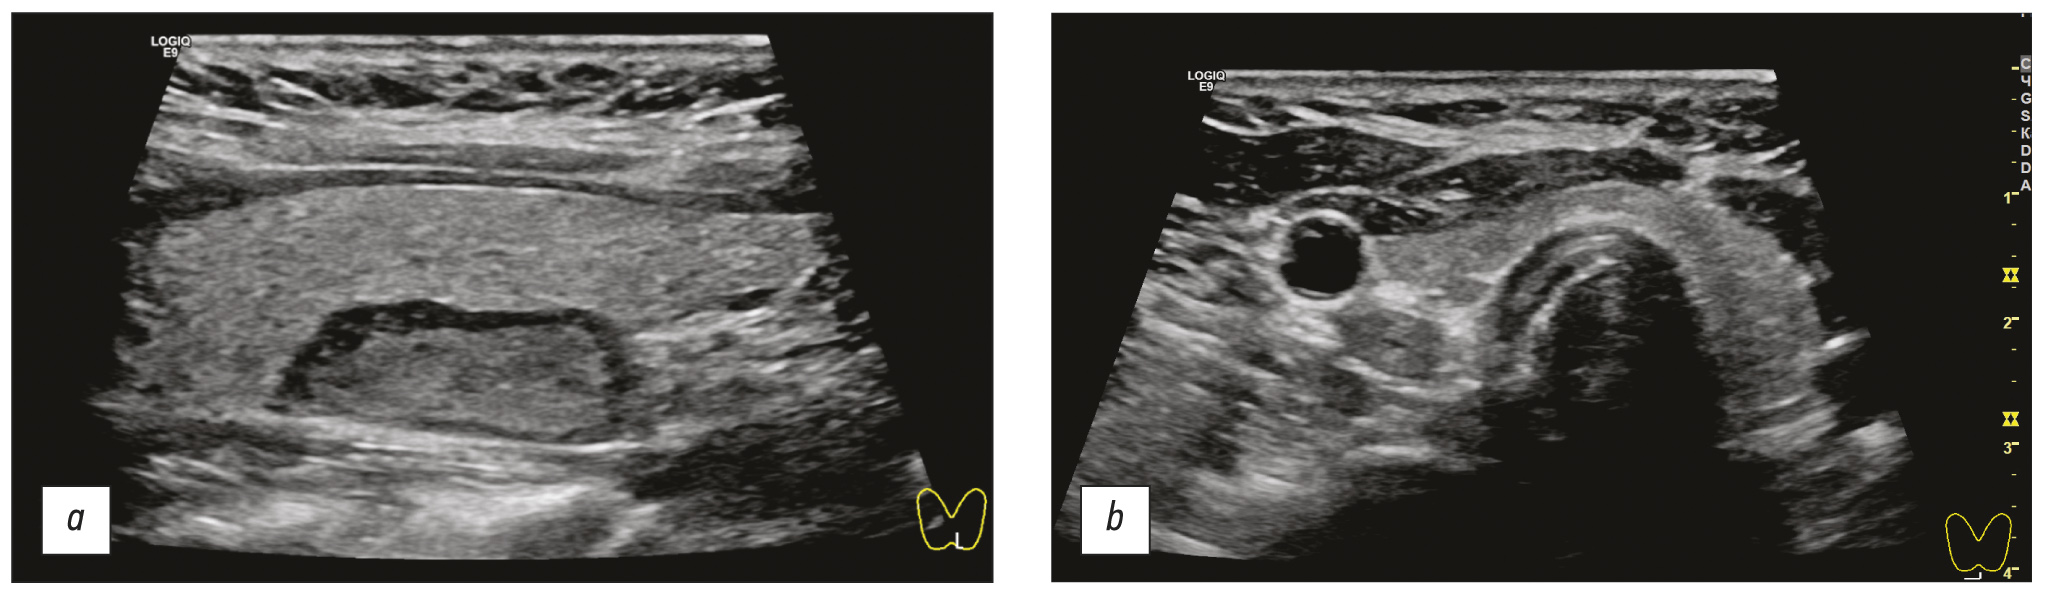

HPT术前成像的标准、最经济和最安全的方法是超声(图 2)。

图 2甲状旁腺功能亢进的甲状旁腺功能亢进的超声成像:a - 原发性甲状旁腺功能亢进; b - 继发性甲状旁腺功能亢进。

当使用微创技术切除甲状旁腺时,术前和术中成像方法的互补性是病理结构定位的一个重要因素(图5)。